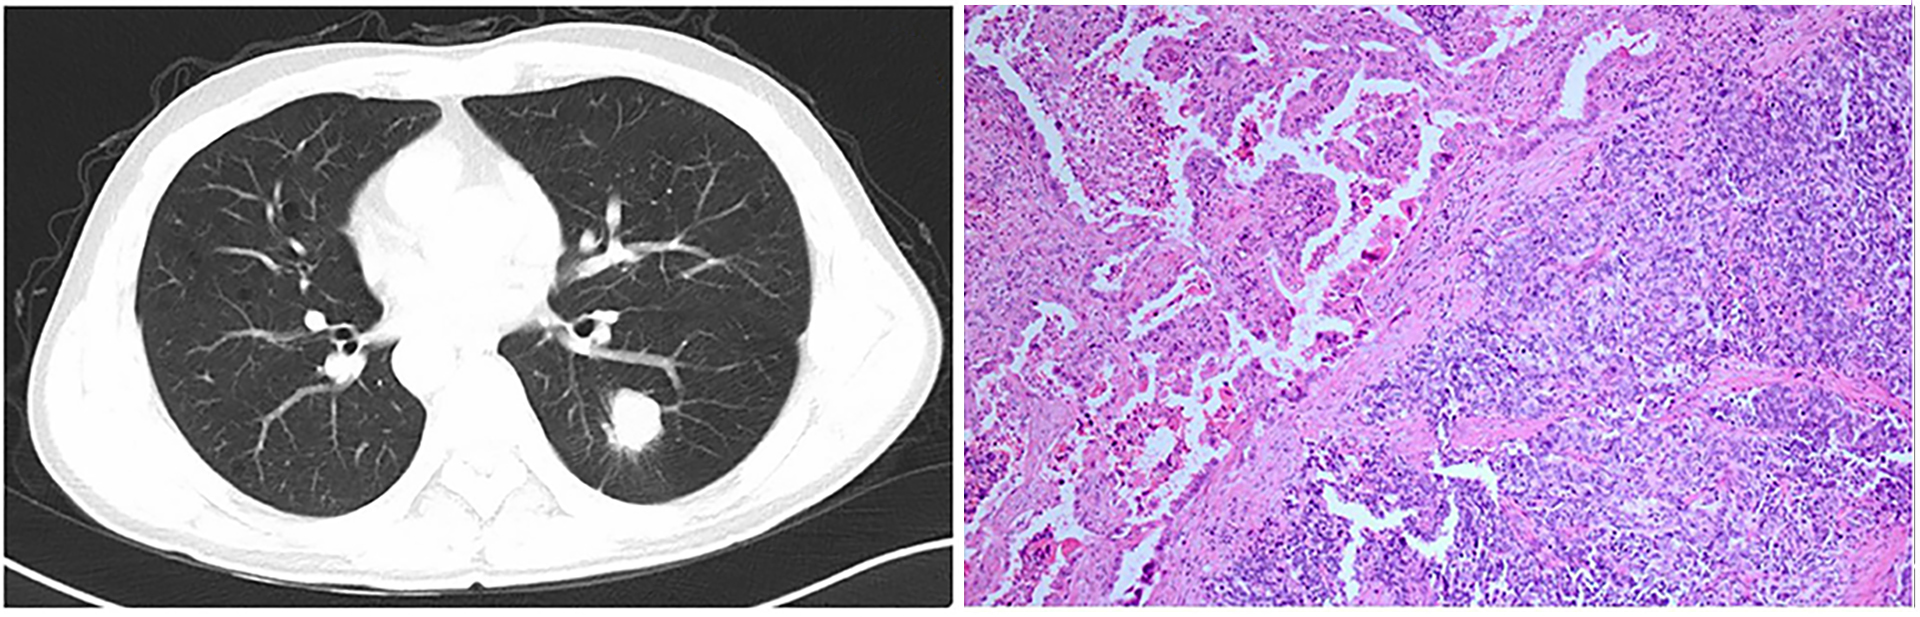

Diagnosis in Singapore

In Singapore, Stage 4 lung cancer is often discovered inadvertently through a chest X-ray or CT scan. A lung cancer specialist, like Dr Harish, will likely suggest several scans to map out where the cancer is accurately to avoid treatments that might not be necessary. MRIs can help check whether the cancer has spread to the brain or spinal cord. CT scans examine the chest and other organs, and PET scans highlight areas of active disease across the body. Bone scans might be used if there’s a suspicion of cancer having spread to the bones.

A tissue biopsy is essential so doctors can recommend a bronchoscopy, an EBUS-guided lymph node biopsy, a CT-guided biopsy, or a test of the fluid around the lung. Molecular profiling and PD-L1 testing are also helpful in deciding the best treatment plan, which might include targeted therapy and immunotherapy.